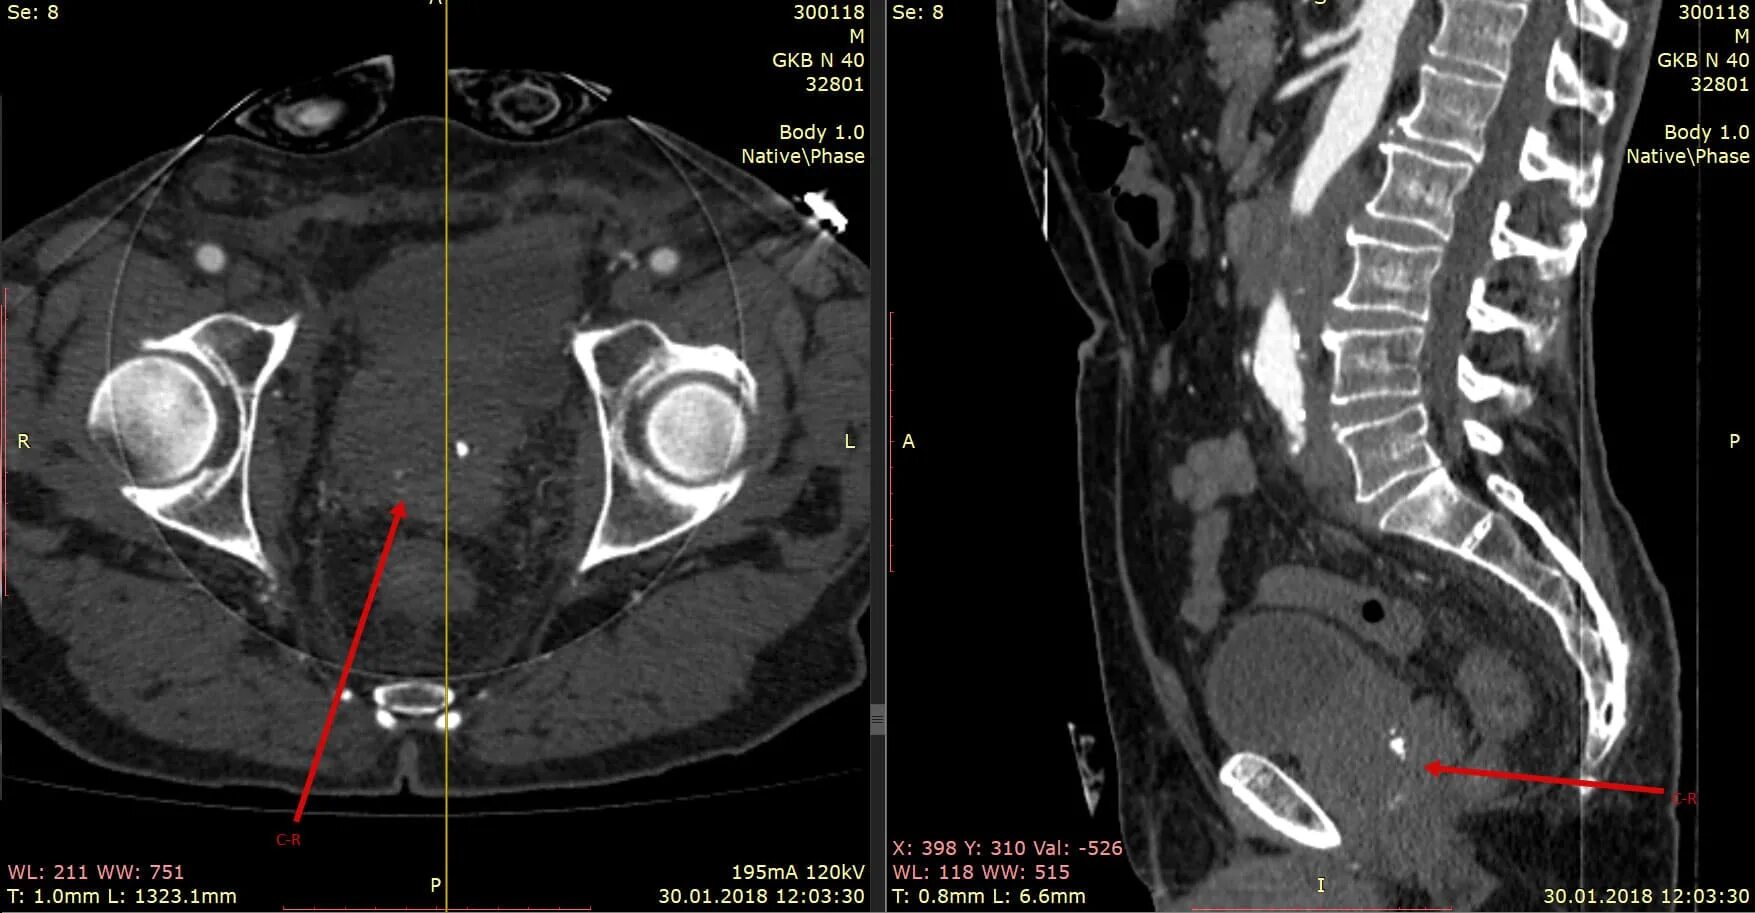

Кт ошибочно